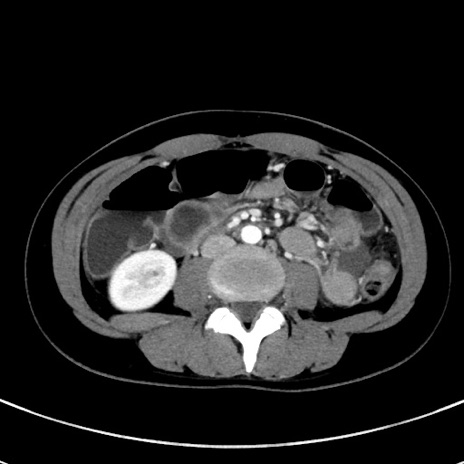

症例17(横断像)

【症例】20歳代女性

【主訴】嘔吐、下腹部痛

【現病歴】昨日夕食後に嘔吐し下腹部痛が出現。本日になっても嘔吐持続し改善しないため来院。

【身体所見】意識清明、BT 37.2℃、BP 108/67mmHg、腹部:平坦、やや硬、下腹部正中から右にかけて圧痛あり、反跳痛軽度あり、tapping pain(+)。

【データ】WBC 13600、CRP 14.94